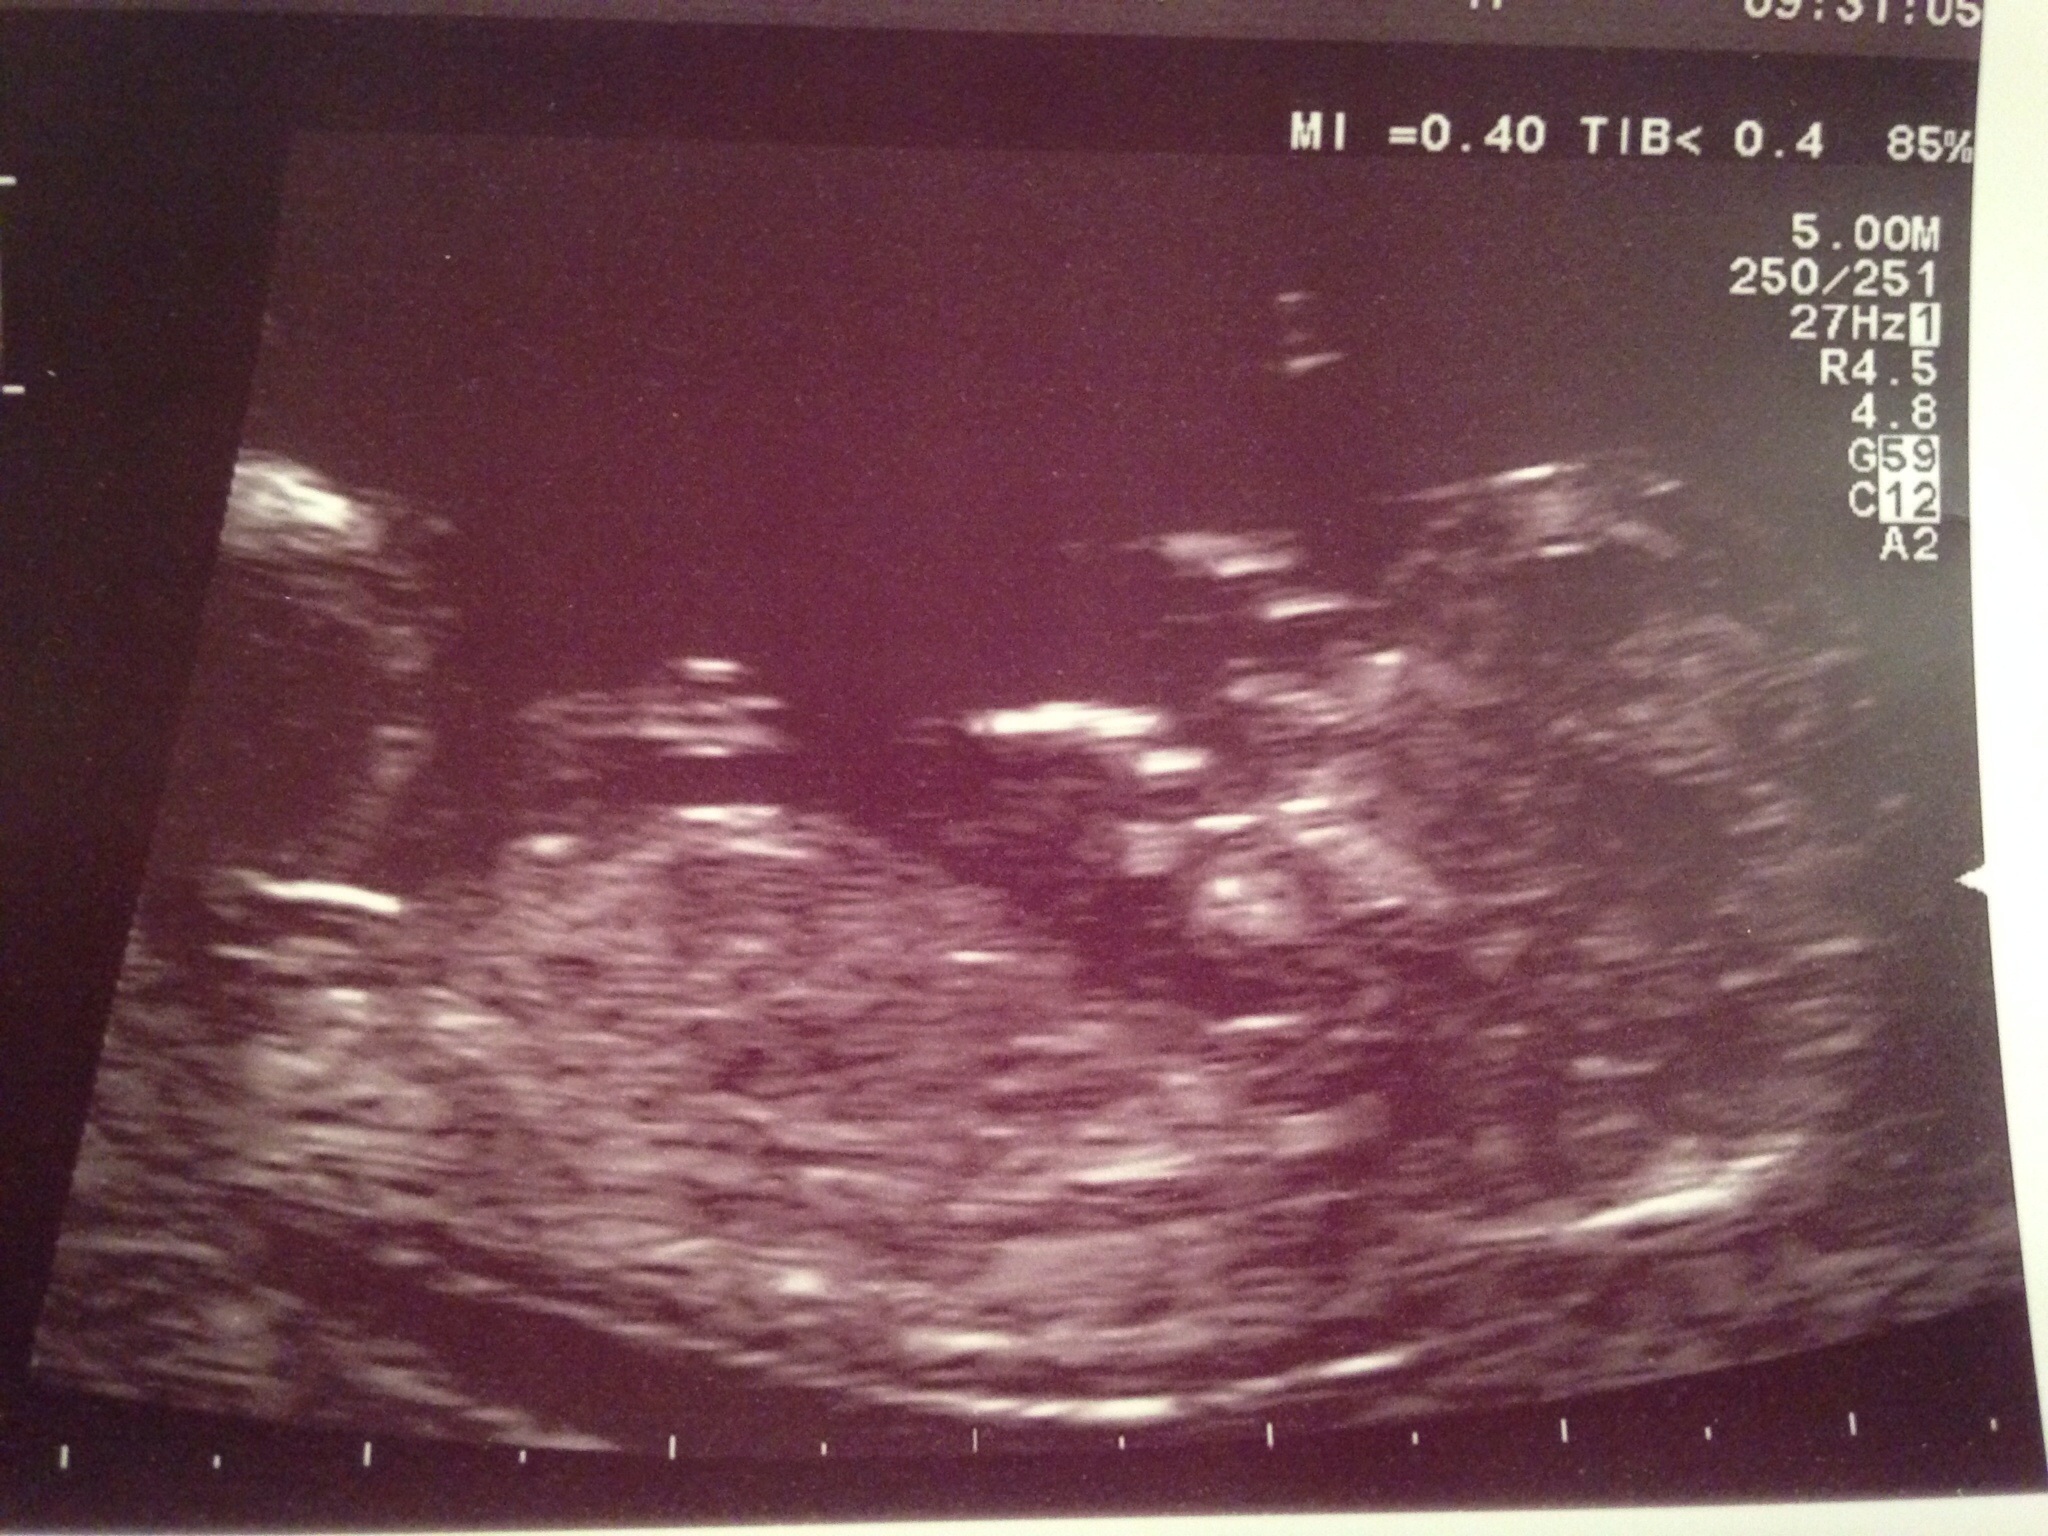

12+3 scan today! What do you think...just for fun :/)